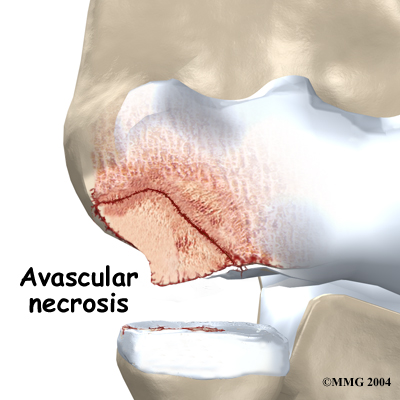

These actions done over and over again can eventually cause an overuse injury to the humeroradial joint of adolescent athletes. Adolescents' articular cartilage is newly formed and so can't handle these types of forces. The subchondral bone (under the articular cartilage) in the capitellum takes the brunt of the stress. A portion of the bone may eventually weaken, and possibly even crack. When the bone is damaged, the tiny blood supply going to the area is somehow blocked. Without blood supply, the small area of bone dies. This type of cell death is called avascular necrosis. ( Avascular means without blood, and necrosis means death.)

As the crack progresses, it may begin to separate. Eventually, the small piece of dead bone may break loose. This produces a separation between the articular cartilage and the subchondral bone, which is a condition called OCD. If the dead piece of bone completely detaches, it becomes a loose body that is free to float around the joint.